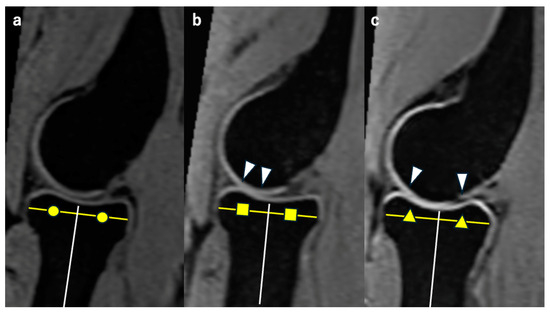

We evaluated the differences in HACV values with and without traction among different age groups (20s, 30s, and 40s) and assessed the effects of traction within each age group. Representative MR images of the RCJ without axial traction in each age group are shown in Figure 2.

Figure 2. Representative MR sagittal images without traction from each age group. Each image passes through the midpoint of the radial head on the coronal image. We measured the JW on a vertical line extending proximally from the white line, which is the bisector of the radial head. The yellow lines represent the diameter of the radial head. Circles, squares and triangles in each figure represent that each white line divides the yellow line equally, making the white lines bisectors. (a) Representative image from the 20s. The HACV is classified as complete. (b) Representative image from the 30s. The HACV is classified as intermediate. The cartilage outline is not visible in the area between white arrowheads. (c) Representative image from the 40s. The HACV is classified as poor. The cartilage outline is not visible in the area between white arrowheads.